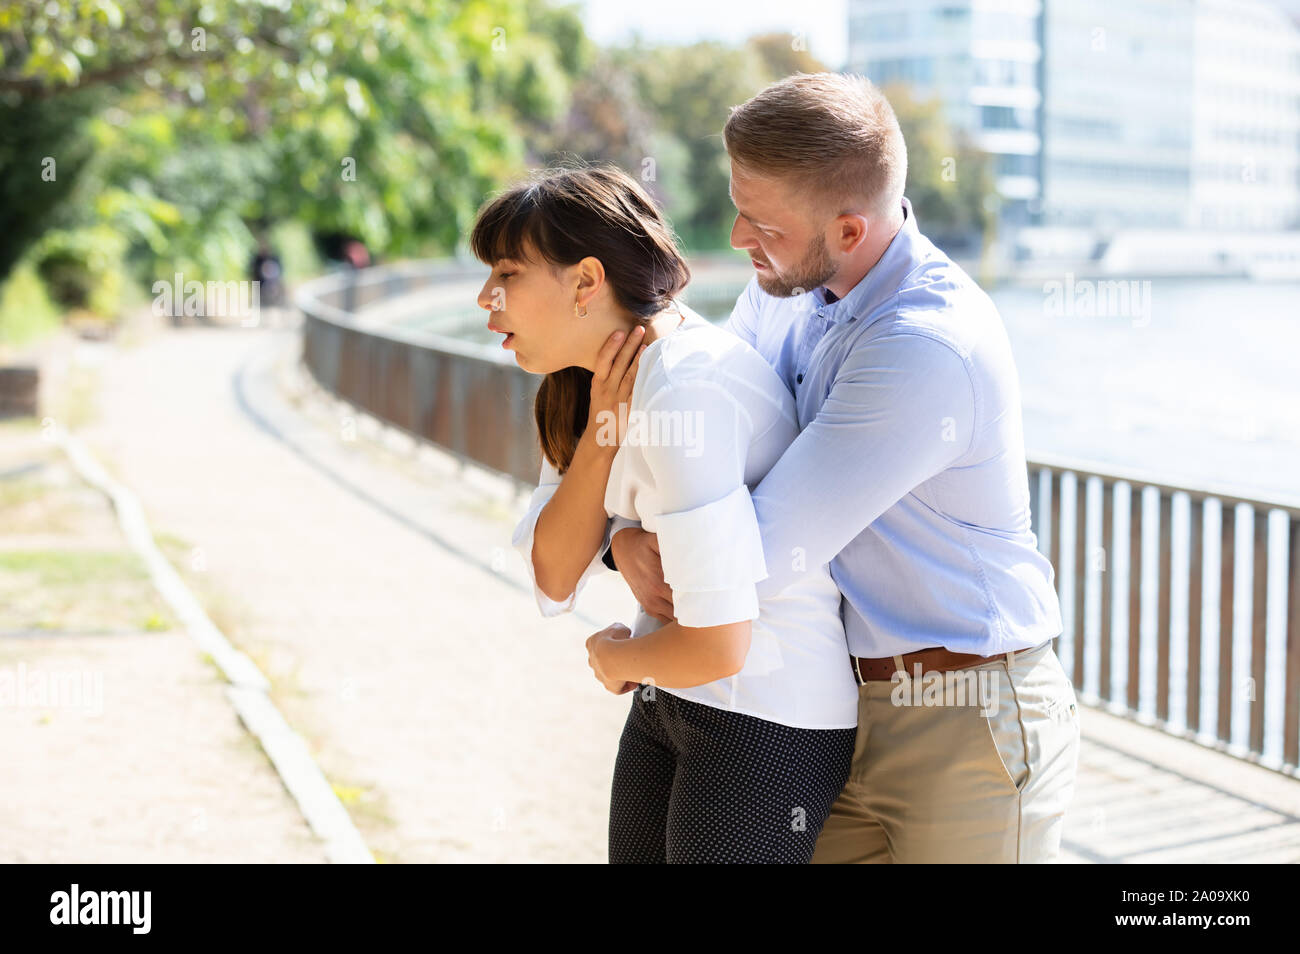

Man Helping Choking Woman To Expel A Trapped Object From Airway. Heimlich Maneuver Stock Photohttps://www.alamy.com/image-license-details/?v=1https://www.alamy.com/man-helping-choking-woman-to-expel-a-trapped-object-from-airway-heimlich-maneuver-image327215476.html

Man Helping Choking Woman To Expel A Trapped Object From Airway. Heimlich Maneuver Stock Photohttps://www.alamy.com/image-license-details/?v=1https://www.alamy.com/man-helping-choking-woman-to-expel-a-trapped-object-from-airway-heimlich-maneuver-image327215476.htmlRF2A09XK0–Man Helping Choking Woman To Expel A Trapped Object From Airway. Heimlich Maneuver

Man Helping Choking Woman To Expel A Trapped Object From Airway. Heimlich Maneuver Stock Photohttps://www.alamy.com/image-license-details/?v=1https://www.alamy.com/man-helping-choking-woman-to-expel-a-trapped-object-from-airway-heimlich-maneuver-image362904342.html

Man Helping Choking Woman To Expel A Trapped Object From Airway. Heimlich Maneuver Stock Photohttps://www.alamy.com/image-license-details/?v=1https://www.alamy.com/man-helping-choking-woman-to-expel-a-trapped-object-from-airway-heimlich-maneuver-image362904342.htmlRF2C2BM5A–Man Helping Choking Woman To Expel A Trapped Object From Airway. Heimlich Maneuver

Man Helping Choking Woman To Expel A Trapped Object From Airway. Heimlich Maneuver Stock Photohttps://www.alamy.com/image-license-details/?v=1https://www.alamy.com/man-helping-choking-woman-to-expel-a-trapped-object-from-airway-heimlich-maneuver-image327215172.html

Man Helping Choking Woman To Expel A Trapped Object From Airway. Heimlich Maneuver Stock Photohttps://www.alamy.com/image-license-details/?v=1https://www.alamy.com/man-helping-choking-woman-to-expel-a-trapped-object-from-airway-heimlich-maneuver-image327215172.htmlRF2A09X84–Man Helping Choking Woman To Expel A Trapped Object From Airway. Heimlich Maneuver

Man Helping Choking Woman To Expel A Trapped Object From Airway. Heimlich Maneuver Stock Photohttps://www.alamy.com/image-license-details/?v=1https://www.alamy.com/man-helping-choking-woman-to-expel-a-trapped-object-from-airway-heimlich-maneuver-image362904343.html

Man Helping Choking Woman To Expel A Trapped Object From Airway. Heimlich Maneuver Stock Photohttps://www.alamy.com/image-license-details/?v=1https://www.alamy.com/man-helping-choking-woman-to-expel-a-trapped-object-from-airway-heimlich-maneuver-image362904343.htmlRF2C2BM5B–Man Helping Choking Woman To Expel A Trapped Object From Airway. Heimlich Maneuver